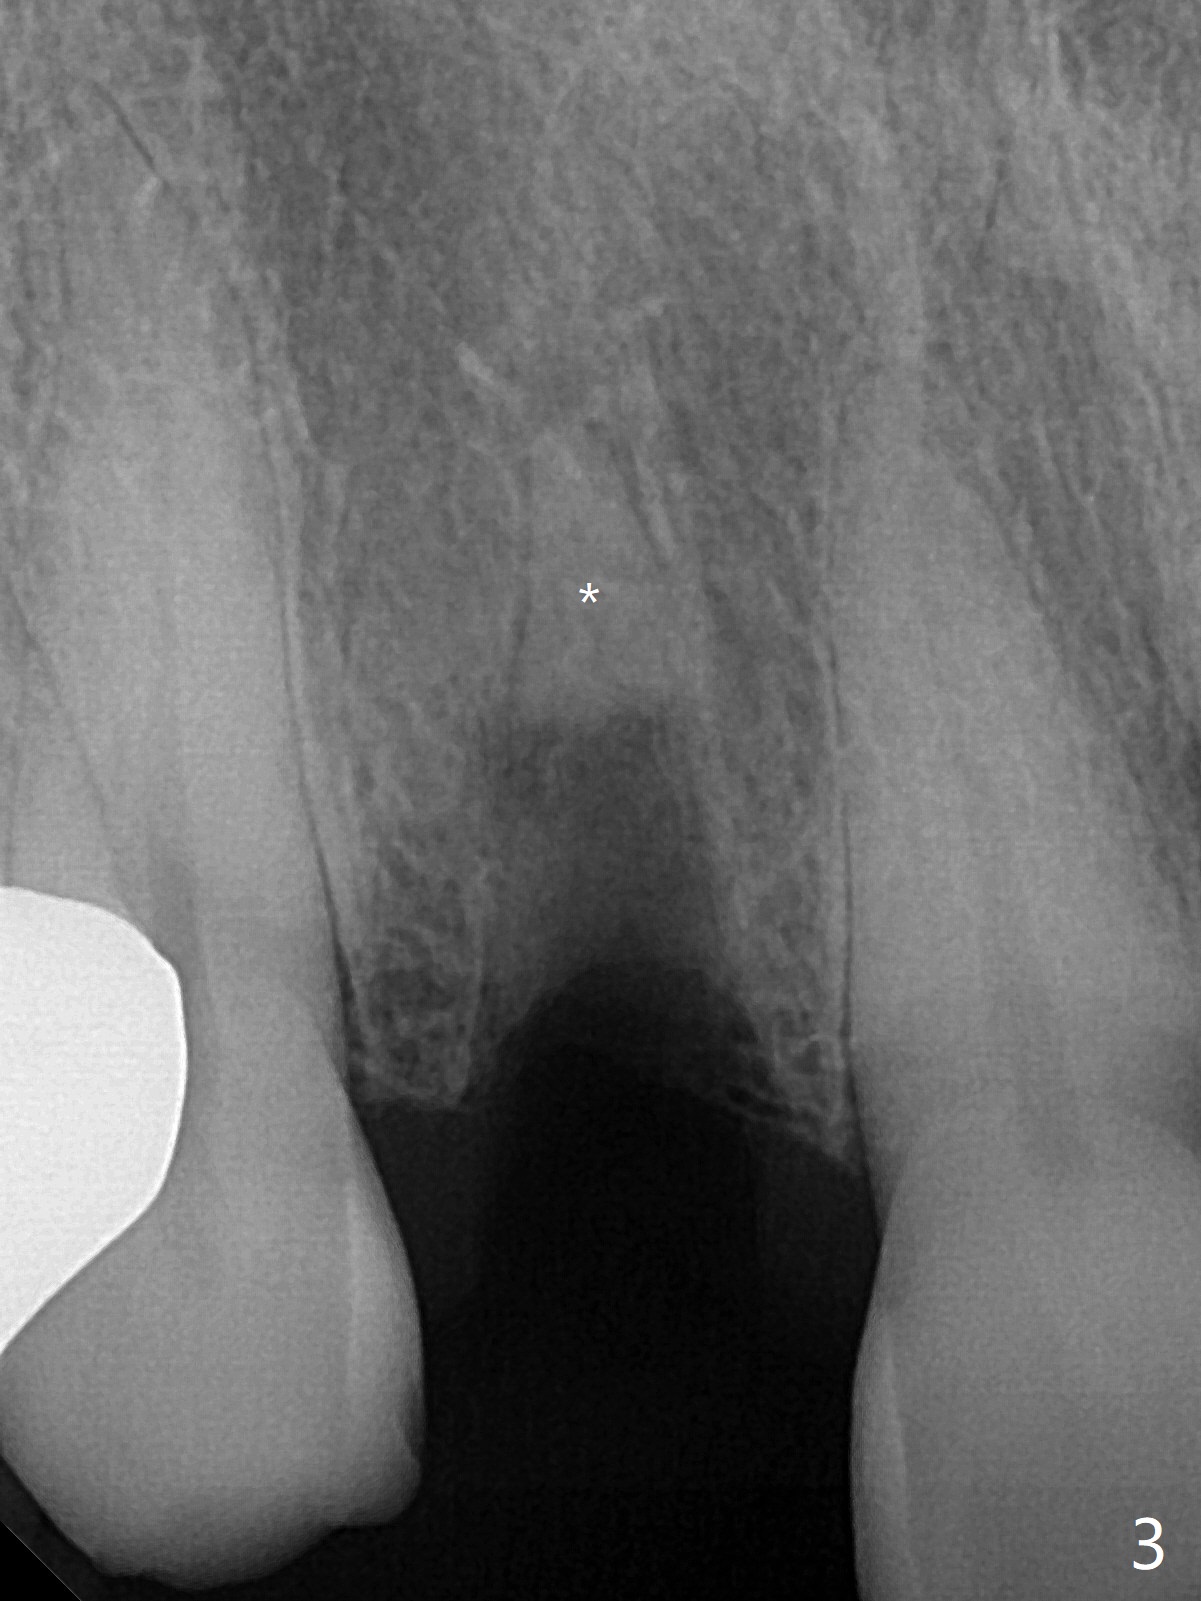

The rebonded crown at #7 debonds in a few days. There is deep anterior overbite and buccal concavity (Fig.1 *). The equigingival fracture (Fig.1,2) seems difficult to restore considering lack of posterior support (lower RPD in Fig.1). Buccal shield is tried in spite of the long root. It is not easy to tell whether the infected apex is removed due to the deep socket. In fact the apical buccal plate perforates because of use of surgical handpiece. Finally the buccal shied is removed. PA confirms the retained apex (Fig.3 *). The initial osteotomy with 1.5 mm drill in place is off trajectory (Fig.4). After adjustment of the trajectory of osteotomy (Fig.5), a 3x16(2) mm 1-piece implant is placed within normal limit (10-15 Ncm, Fig.6)). In fact bone graft is placed before (Fig.6,7 arrowhead; to repair apical buccal plate perforation) and after (Fig.6 *) implantation. The gingiva (including papillae) remains normal around the provisional 3 months postop (Fig.8). The bone graft becomes more organized 3 months postop (Fig.9), continues to do so 4.5 months postop (Fig.10) and becomes dense coronally 9 months post cementation (Fig.11: *).